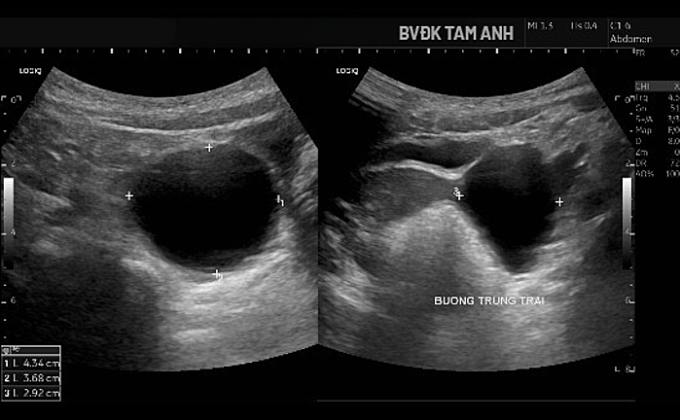

Ngoài ngực phát triển, bé Huyền chưa xuất hiện dấu hiệu dậy thì khác. ThS.BS Đỗ Tiến Sơn, khoa Nhi, Bệnh viện Đa khoa Tâm Anh Hà Nội, ghi nhận tuyến vú của trẻ đã phát triển ở giai đoạn Tanner B3 – giai đoạn bắt đầu xuất hiện mô tuyến vú nhanh và rõ. Buồng trứng trái có nang lớn kích thước khoảng 43x37x29 mm, thành mỏng, chứa dịch trong, bên trong có nang nhỏ. Tổn thương được xếp loại ORADS 2, nguy cơ ác tính thấp. Chụp MRI xác định nang buồng trứng trái lành tính. Kết quả X-quang đánh giá tuổi xương chưa tăng, hiện phù hợp với tuổi thực của bé.

Hình siêu âm cho thấy nang buồng trứng phì đại. Ảnh: Bệnh viện Đa khoa Tâm Anh